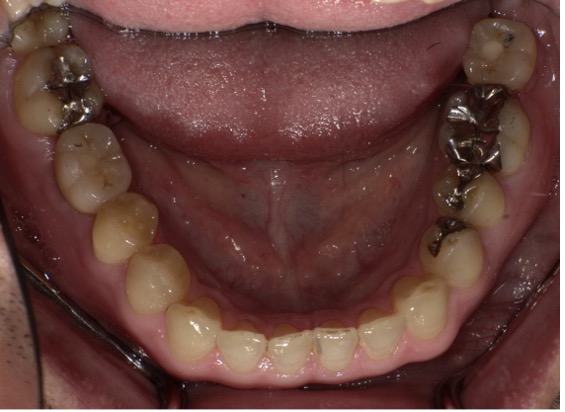

もともと欠損部には何も入れず、反対側も力が加わり根っこが折れてしまい抜歯になったケースです。

右下と左下の欠損部にはインプラント治療をご希望されました。また上あごの前歯が割れており、膿がたまって骨が大きく溶けてしまっていたため、抜歯を行いブリッジ治療を施しました。

【Before】